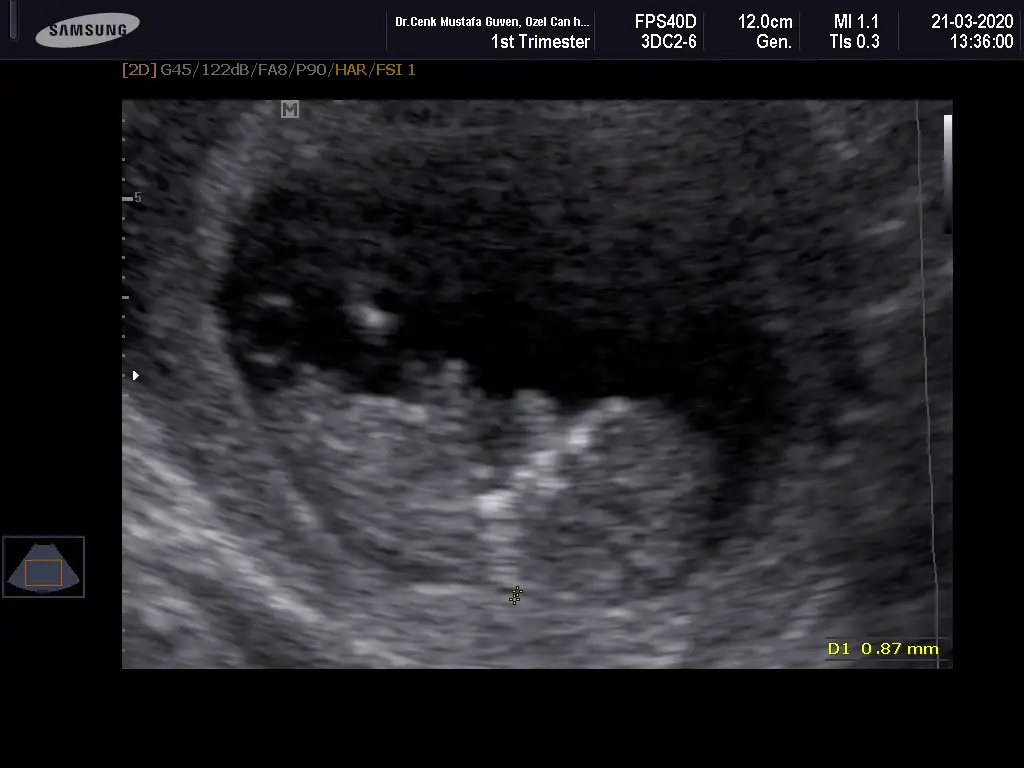

İlk iki foto alttan bakılandan son foto normal daha öncede atmıstım ama cok belli değil demiştiniz bu şekilde bi tahmin olabilirmi Ikra meyra Ikra meyra ☺️